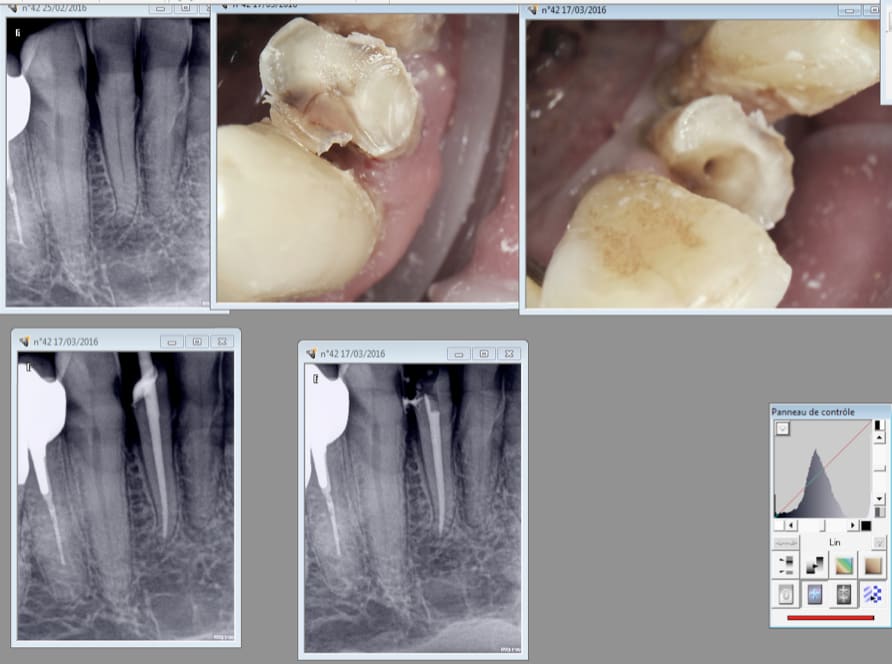

Bonjour à tous, je tiens avant tout à vous remercier pour vos suggestions et voici une radio.

ps: je tiens à préciser que la 42 présentait déjà une obturation canalaire incomplète (comme vous pouvez remarquer).